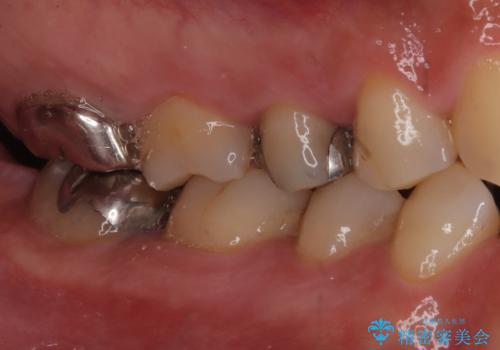

- お口の中にある銀歯を全てなくして、白く健康的な状態にしたい」という主訴でご来院されました。長年使用してきた複数の銀歯は、経年劣化により適合が悪くなっており、一部では内部で二次カリエス(虫歯の再発)も認められました。

患者様と相談の上、全ての金属(メタル)を取り除き、生体親和性が高く審美性に優れた素材へ置き換えるメタルフリー治療の計画を立案。部位や欠損の大きさに合わせ、セラミックインレーおよびセラミッククラウンを用いて、お口全体の調和を整えることとしました。

銀歯の除去と精密な再治療: 古い銀歯を一つひとつ丁寧に取り外し、内部の虫歯を徹底的に除去。神経を保護するための処置を行った上で、適合性を極限まで高めるために精密な型取りを行いました。